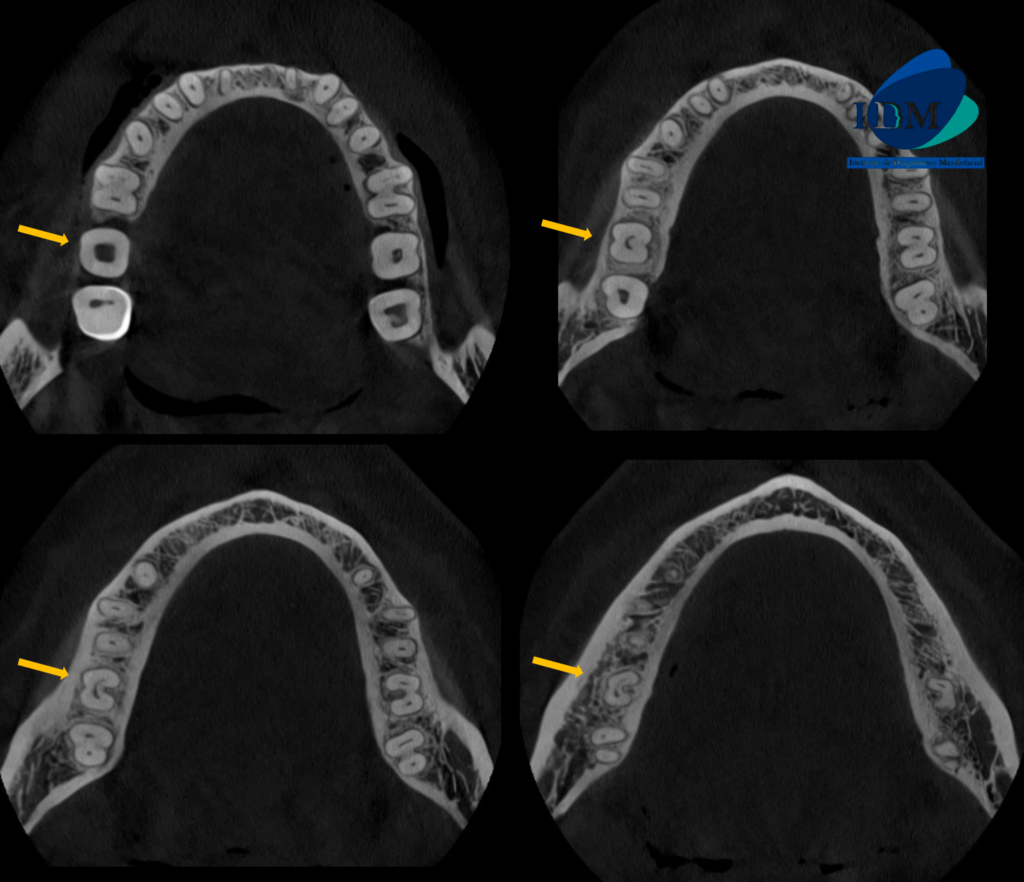

Radiografia Panorámica

En la radiografía panorámica (Figura 1), se observa el engrosamiento de la mucosa de senos maxilares, aparatología ortodóntica en maxilar superior e inferior y múltiples restauraciones coronarias; a nivel de las piezas 37 y 47 se observa la elongación céfalo – caudal de la cámara pulpar, compatible con taurodontismo.